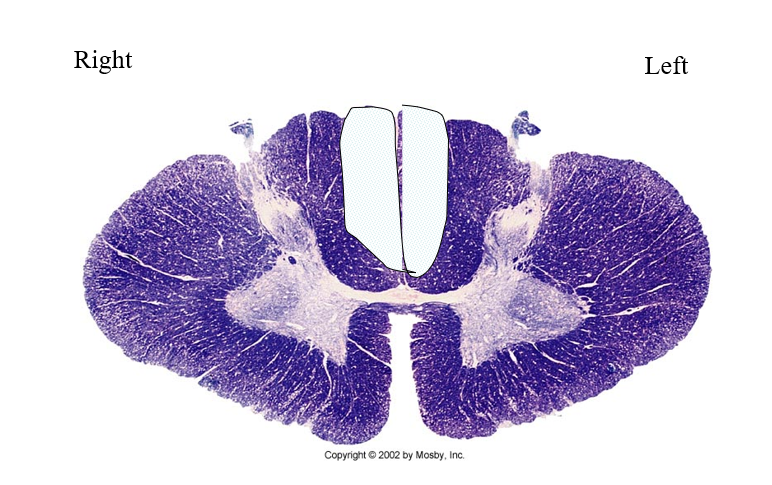

Brown-sequard syndrome

Subacute Degeneration of the cord